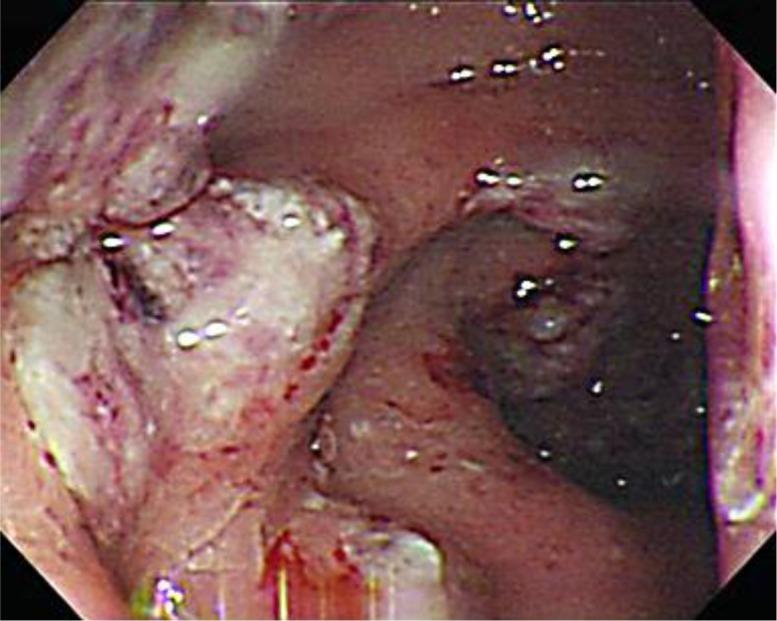

Ameboma is a rare complication of amebic colitis presenting as a mass of granulation tissue with peripheral fibrosis and a core of inflammation related to amebic chronic infection. The initial presentations are usually obstruction and low gastrointestinal bleeding. The most common sites are the ascending colon and the cecum. It may mimic colon carcinoma, Crohn's disease, carcinoma of the colon, non-Hodgkin's lymphoma, tuberculosis, fungal infection, AIDS-associated lymphoma and Kaposi's sarcoma in colonoscopy findings. The therapeutic strategy should be combined with antibiotics for invasive dysentery and eradication of luminal cysts.